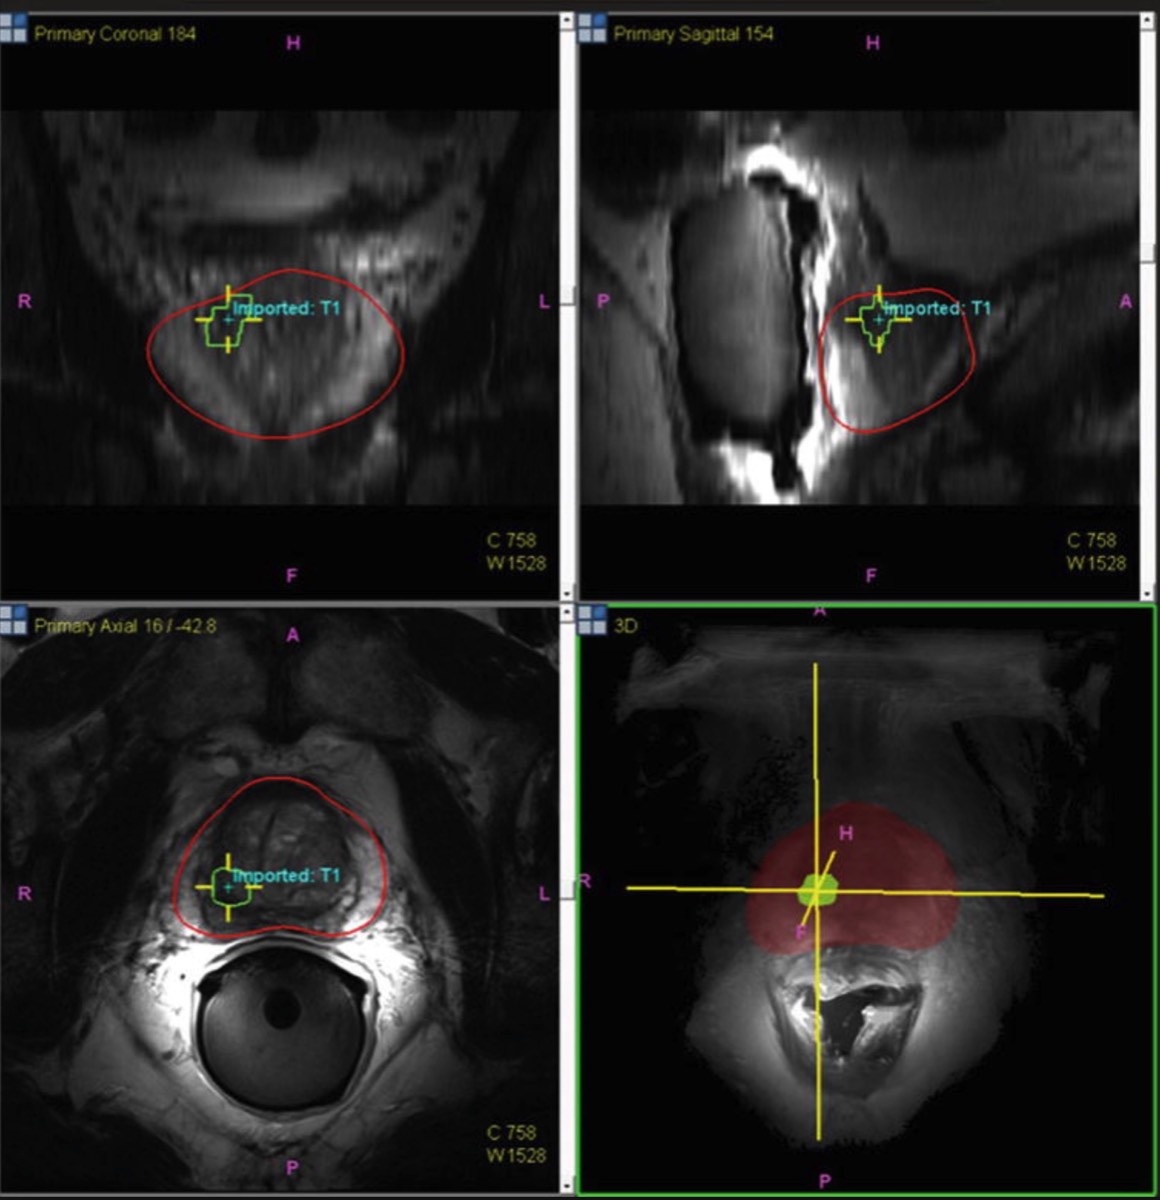

La biopsia por fusión recibe este nombre porque en ella se fusionan las imágenes tomadas en una Resonancia Nuclear Magnética de próstata previa con las imágenes que, en tiempo real, se están obteniendo de la ecografía transrectal intraoperatoria, bien de modo cognitivo o bien empleando un software específico.

Esta técnica supone una revolución en el diagnóstico del cáncer de próstata, ya que nos permite obtener una biopsia dirigida a la zona sospechosa de malignidad, que se puede complementar con un “mapeo” prostático en el mismo momento: Consiste en recoger primero las muestras en las zonas detectadas como sospechosas de tumor, y además se complementa con biopsias sistemáticas (repartidas exactamente cada pocos milímetros) del resto del tejido, lo que hace muy improbable que si existe un tumor de próstata no sea detectado.